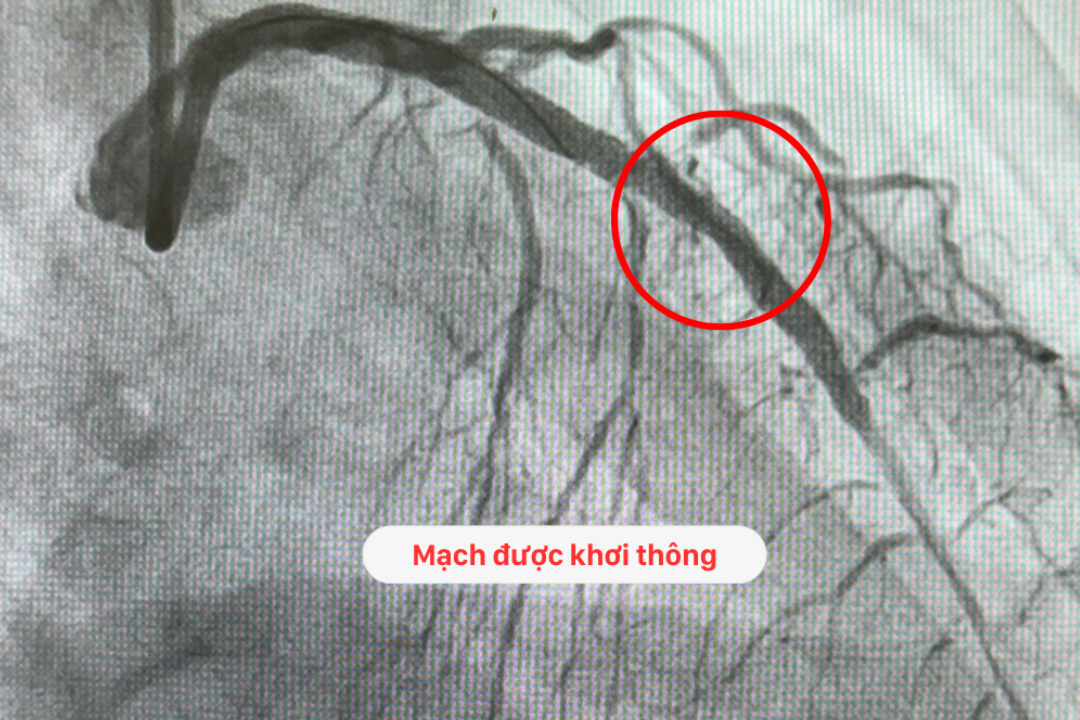

Ngay sau 30 phút kích hoạt tình huống khẩn cấp, Ê kíp bác sĩ BVĐK Hồng Ngọc đã thành công đặt 02 stent từ vị trí lỗ vào thân chung động mạch vành trái tới hết đoạn II của động mạch liên thất trước với kích thước lần lượt là: 3.0 x 30mm và 3.5 x 38mm cho bệnh nhân T.

Kết quả kiểm tra sau can thiệp cho thấy: dòng chảy sau tái thông tốt, stent nở tốt và áp sát thành mạch, huyết áp đảm bảo 95 – 100/60 mmHg, lâm sàng bệnh nhân đỡ đau ngực, đỡ khó thở, cảm thấy dễ chịu hơn.

Hình ảnh tái thông mạch vành thành công cho bệnh nhân T